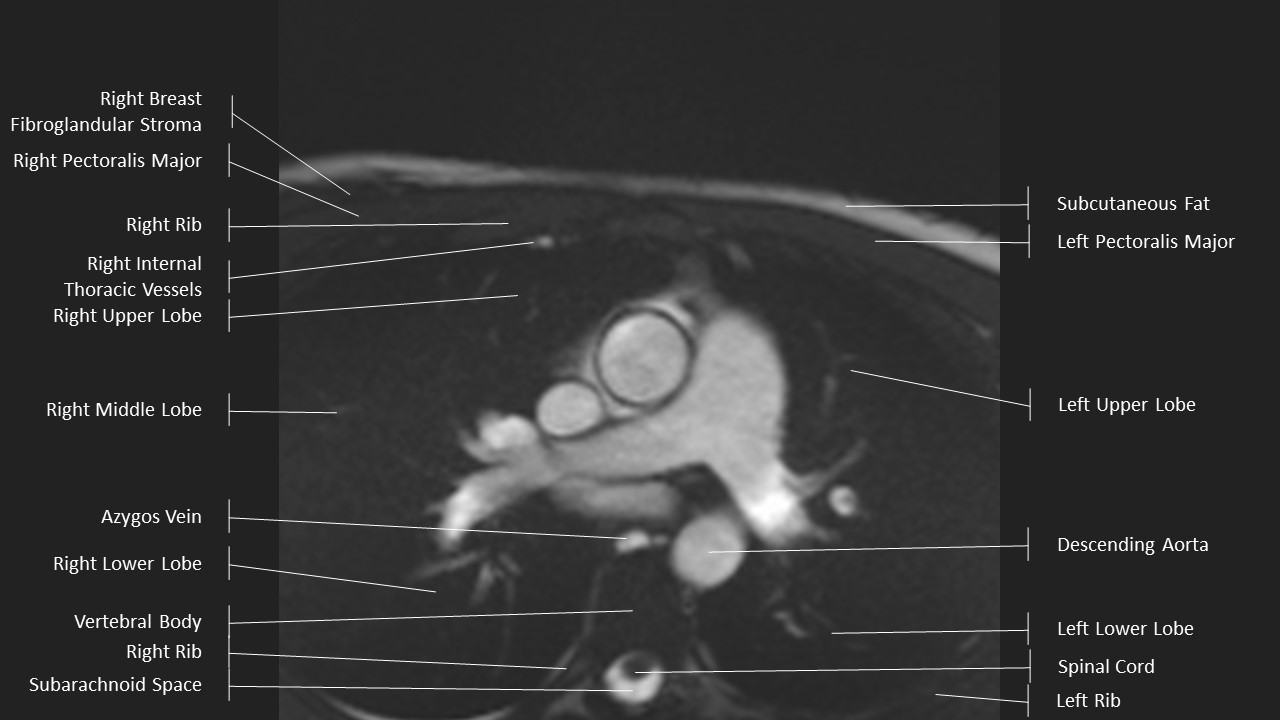

Axial Series